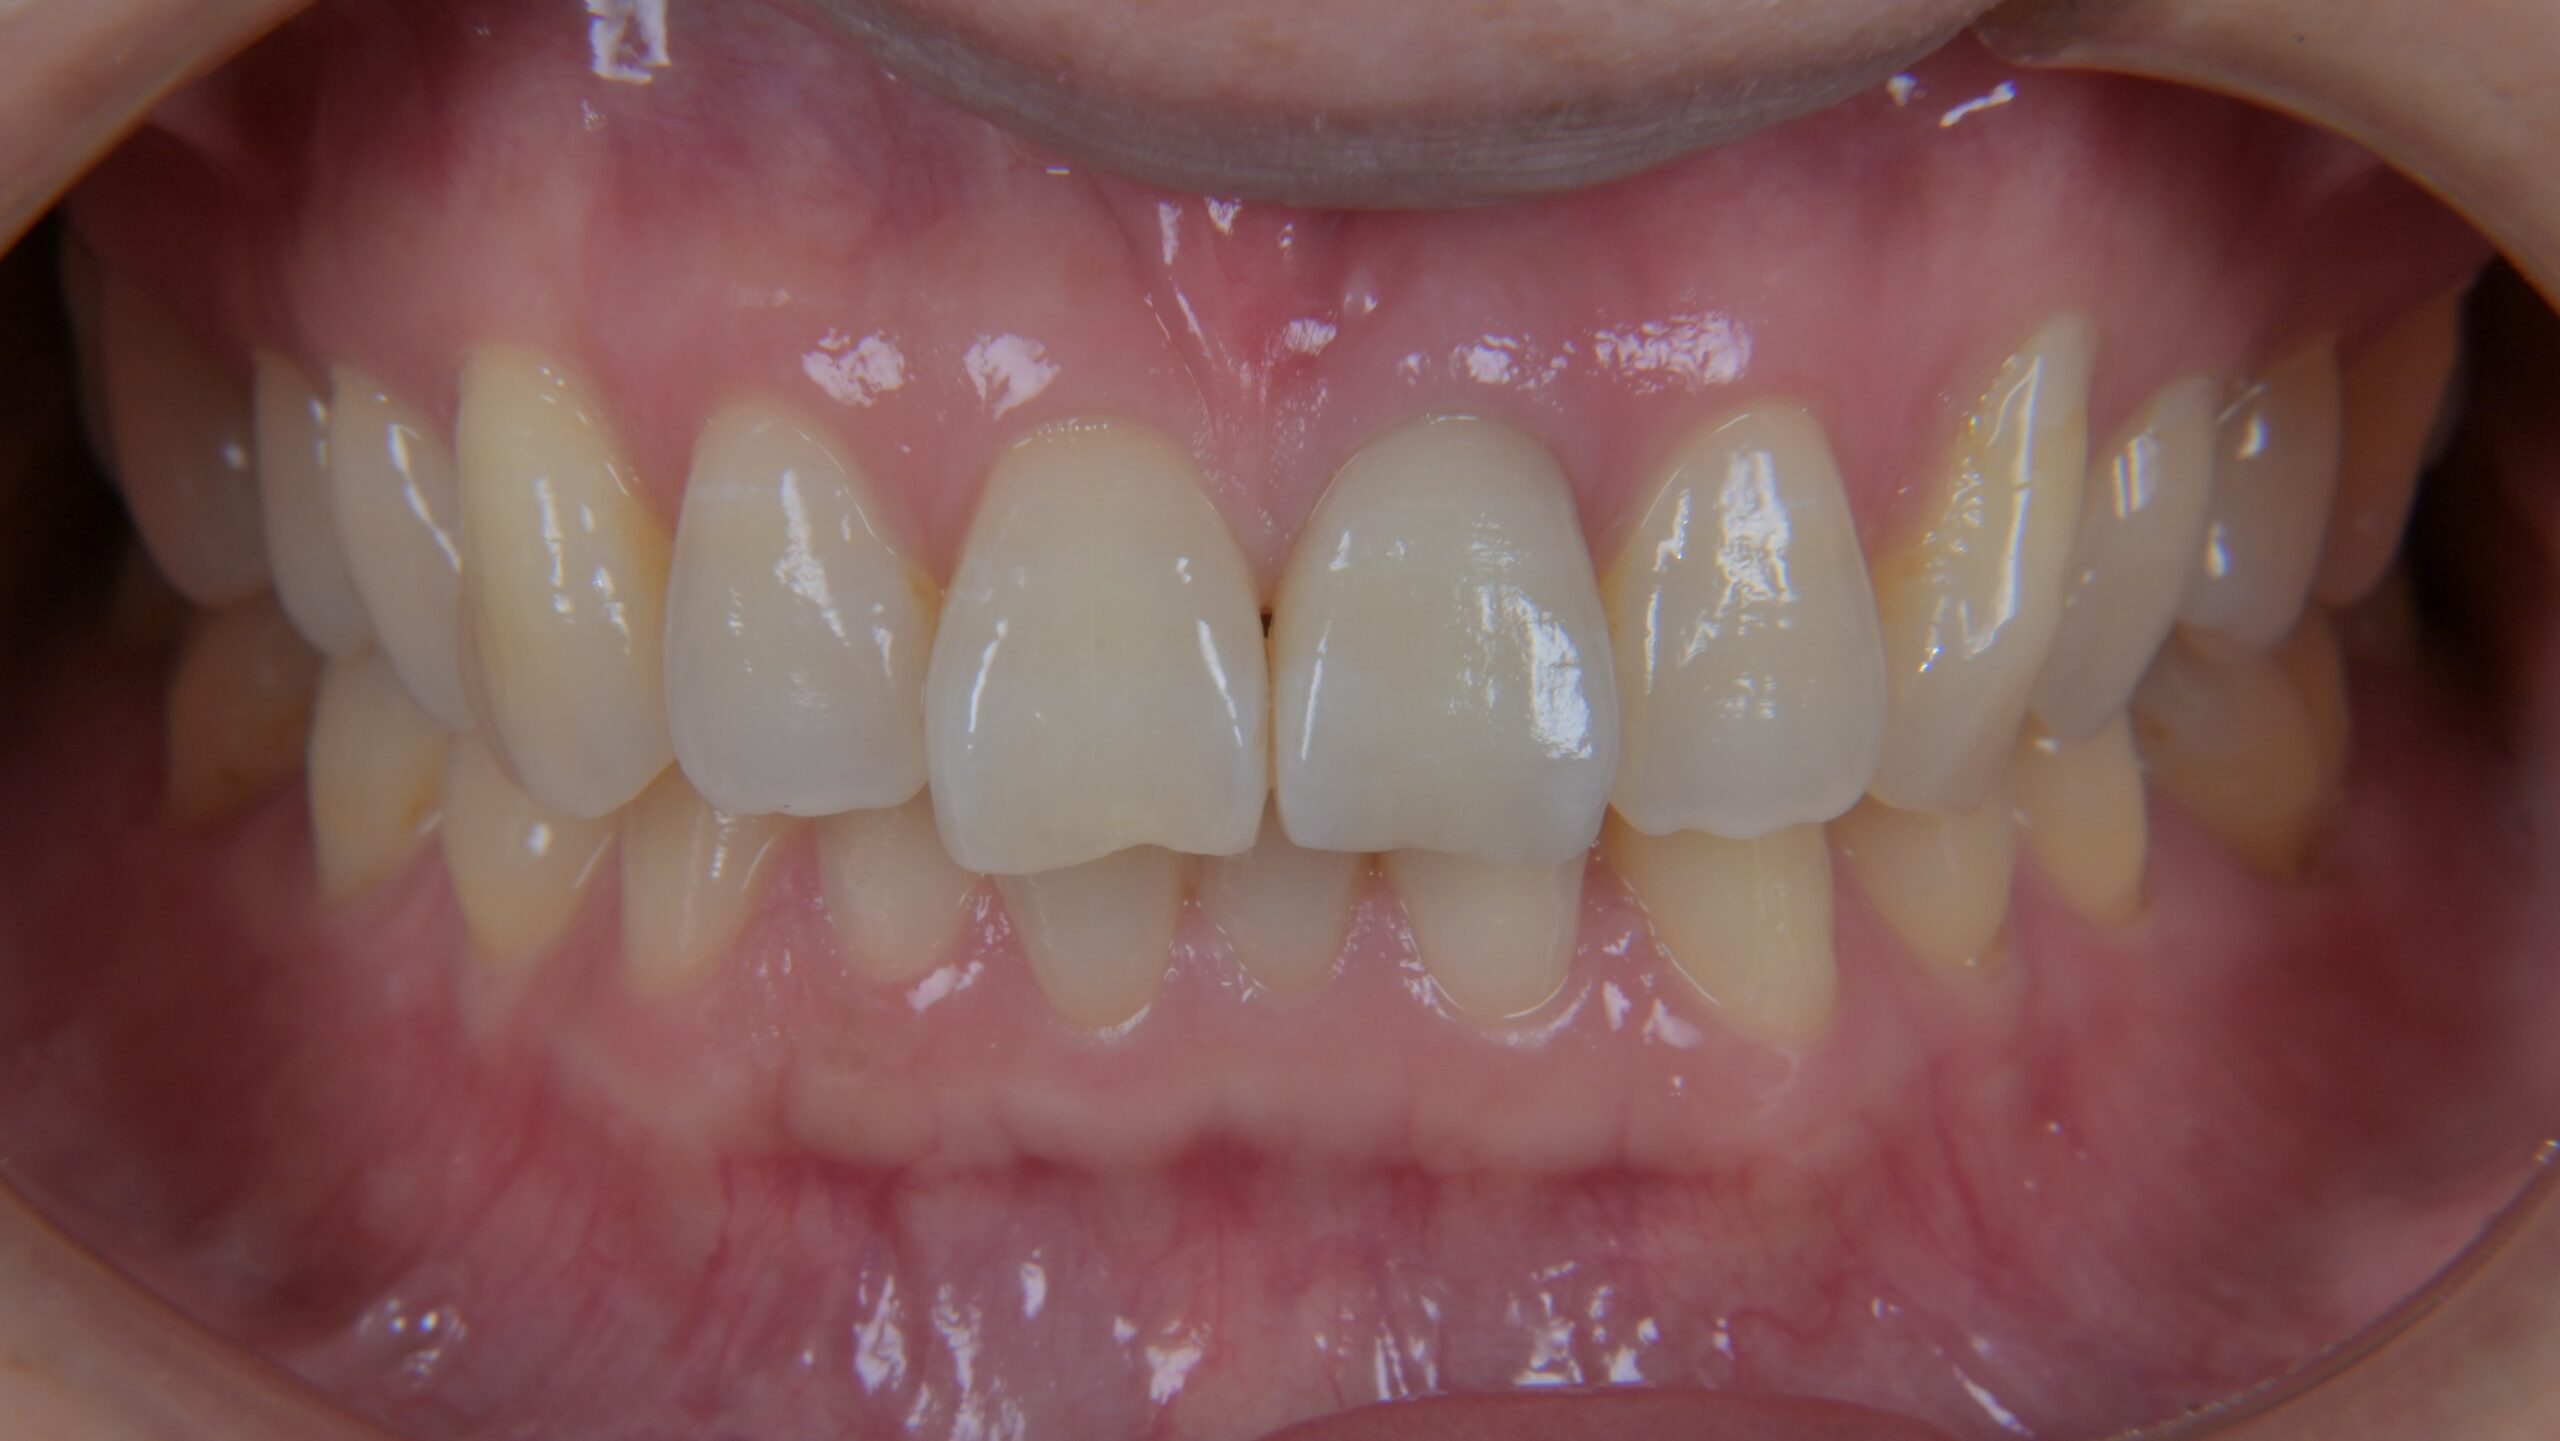

前歯のジルコニアクラウン症例

Before

After

治療内容

左上1番の被せ物に色の違いや、段差があるのが気になる為やり変えを希望されました。

古い被せ物を除去し、1回目の仮歯に置き換えます。

患者様と相談し形態を修正し、2回目の仮歯に移行します。

その後、最終的な被せ物を作るための型取りを行います。

最終的にジルコニアクラウンにて被せ物を接着しました。

担当歯科医師:平沼 佳朗

治療期間・回数

約3回

費用

¥154,000

リスク・副作用

ごく稀にジルコニアクラウンの先端が割れることがあります。